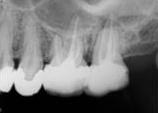

antes depois